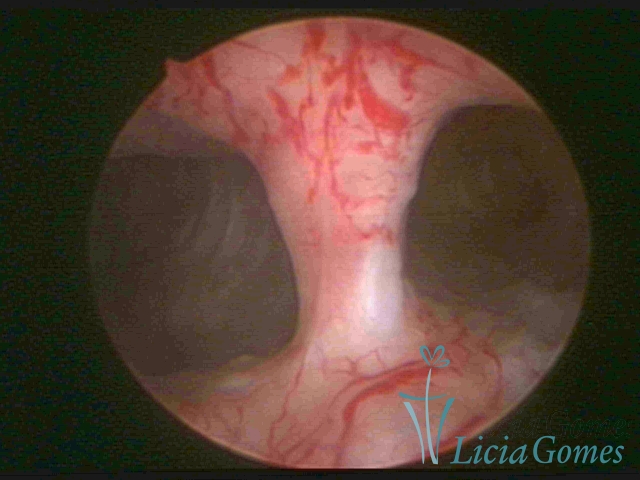

Bicornuate uterus

Malformation in which there is the lack of the flat portion of uterine fundus due to the lack of fusion on the proximal portion of paramesonephric ducts. The uterine fundus has two narrowed spaces in a divergent oblique angulation. It may be complete, from the fundus to the cervix; or partial, completely dividing the uterine cavity.

The tilted uterus which presents the most difficult hysteroscopic diagnosis occurs when there is only a small indentation of the uterine fundus.